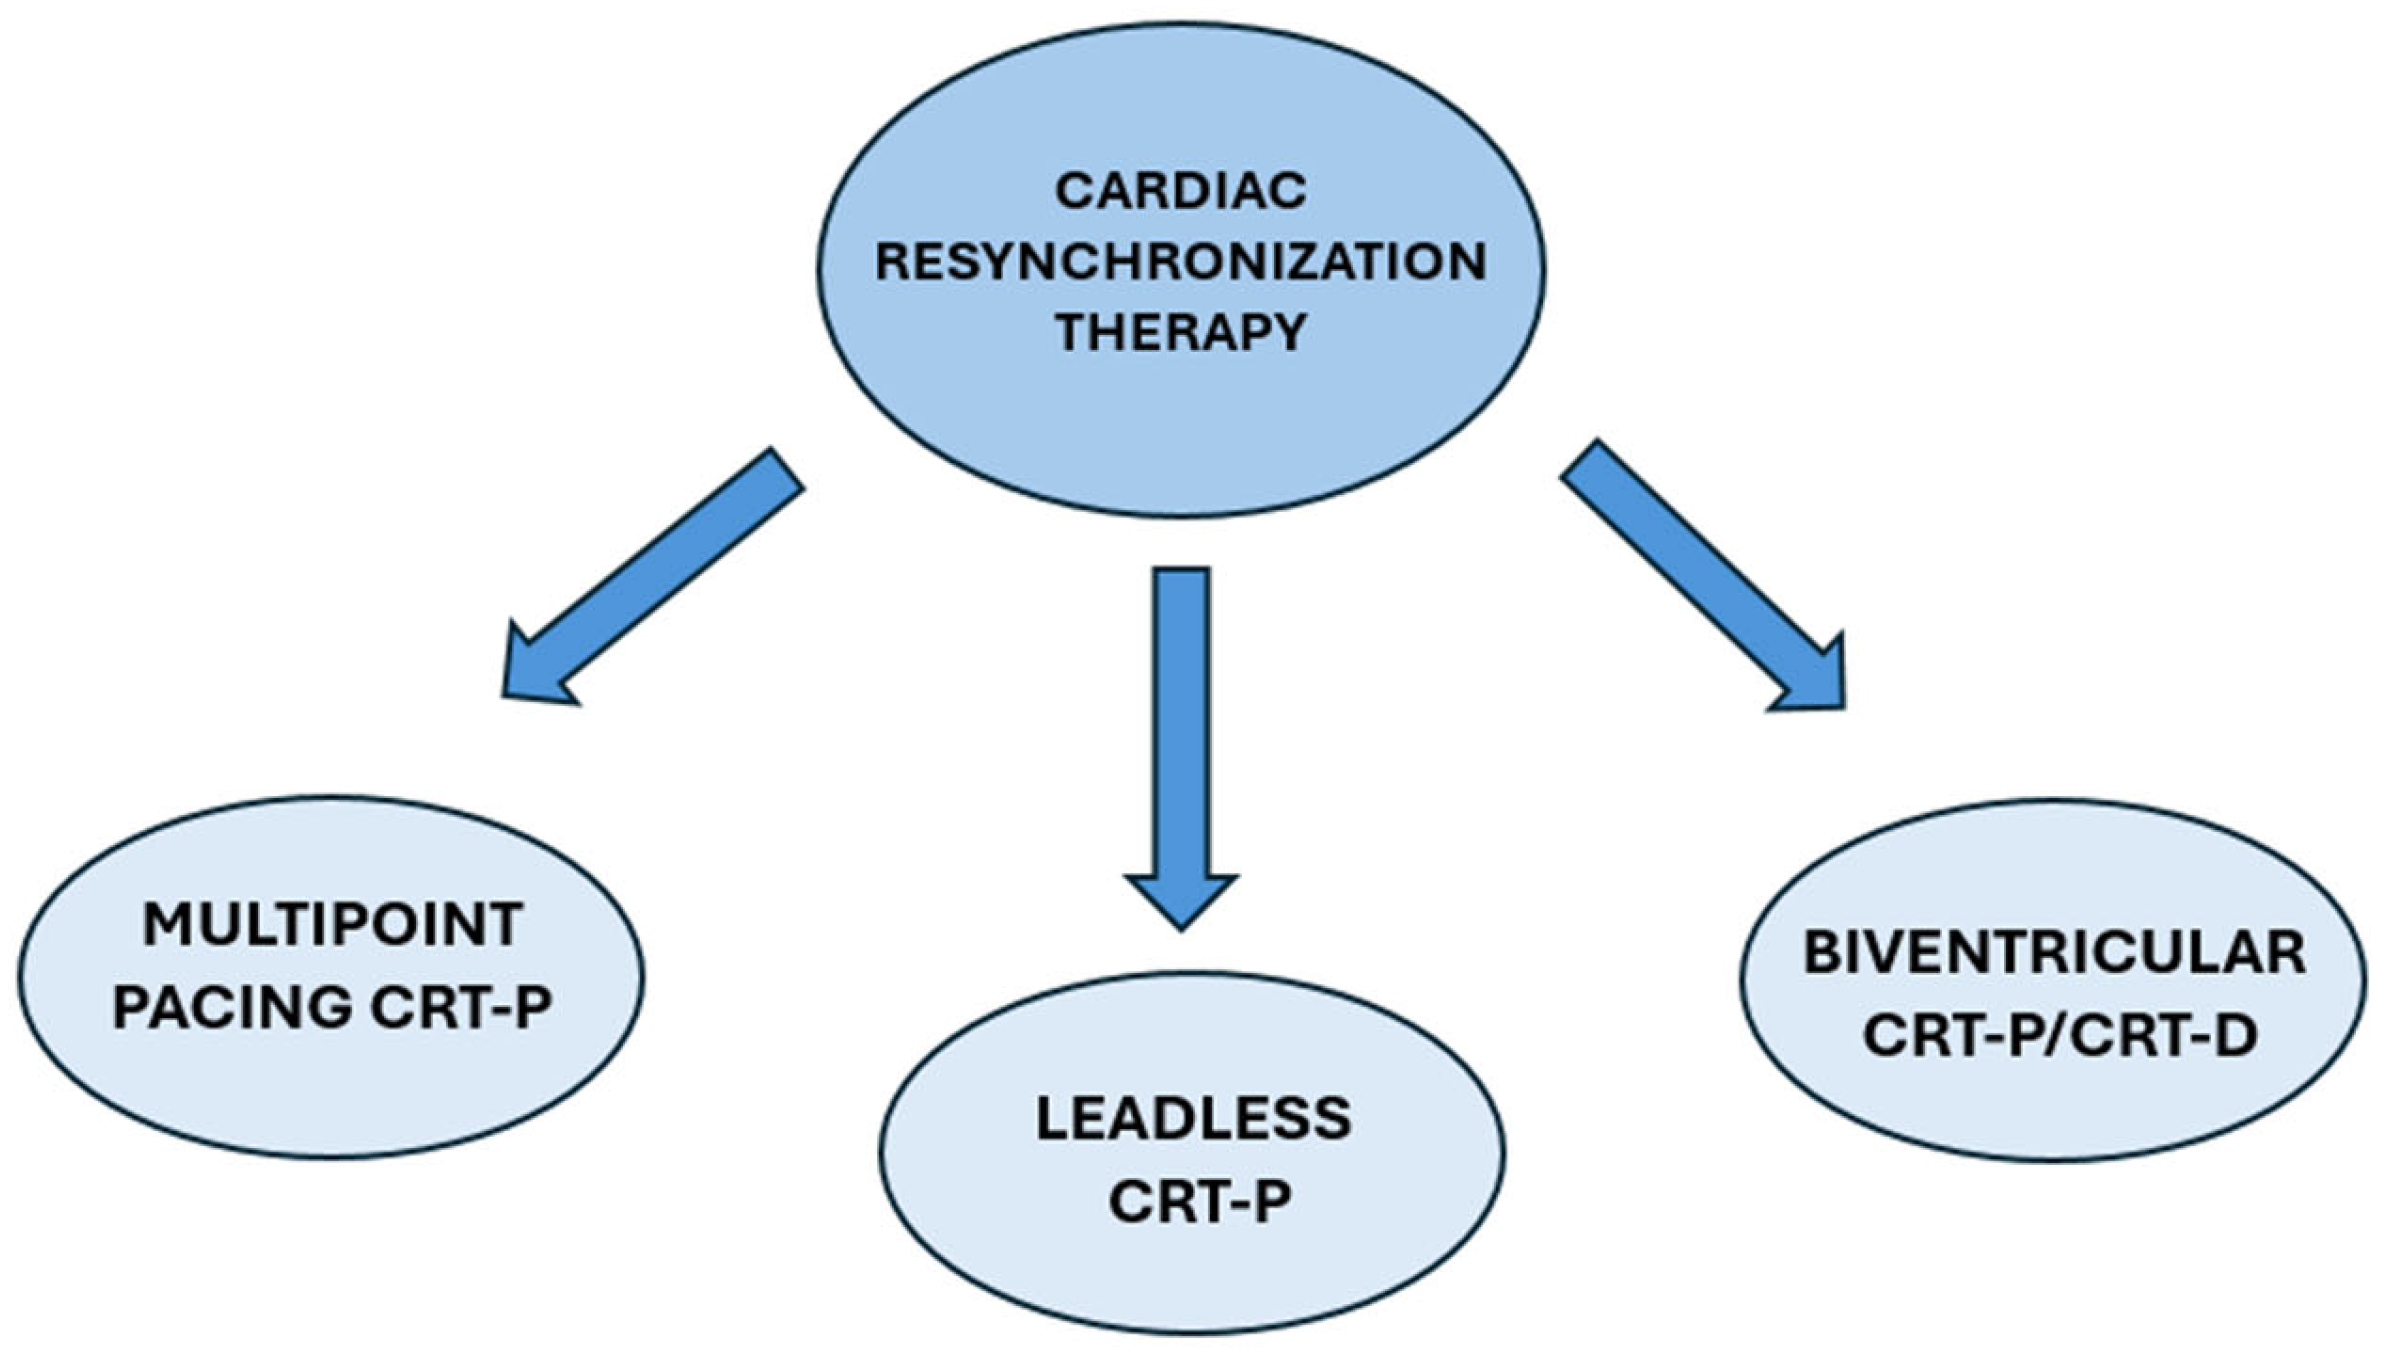

4. Types of CRT

4.1. Biventricular CRT

4.2. Multipoint Pacing CRT

4.3. CRT-Defibrillators